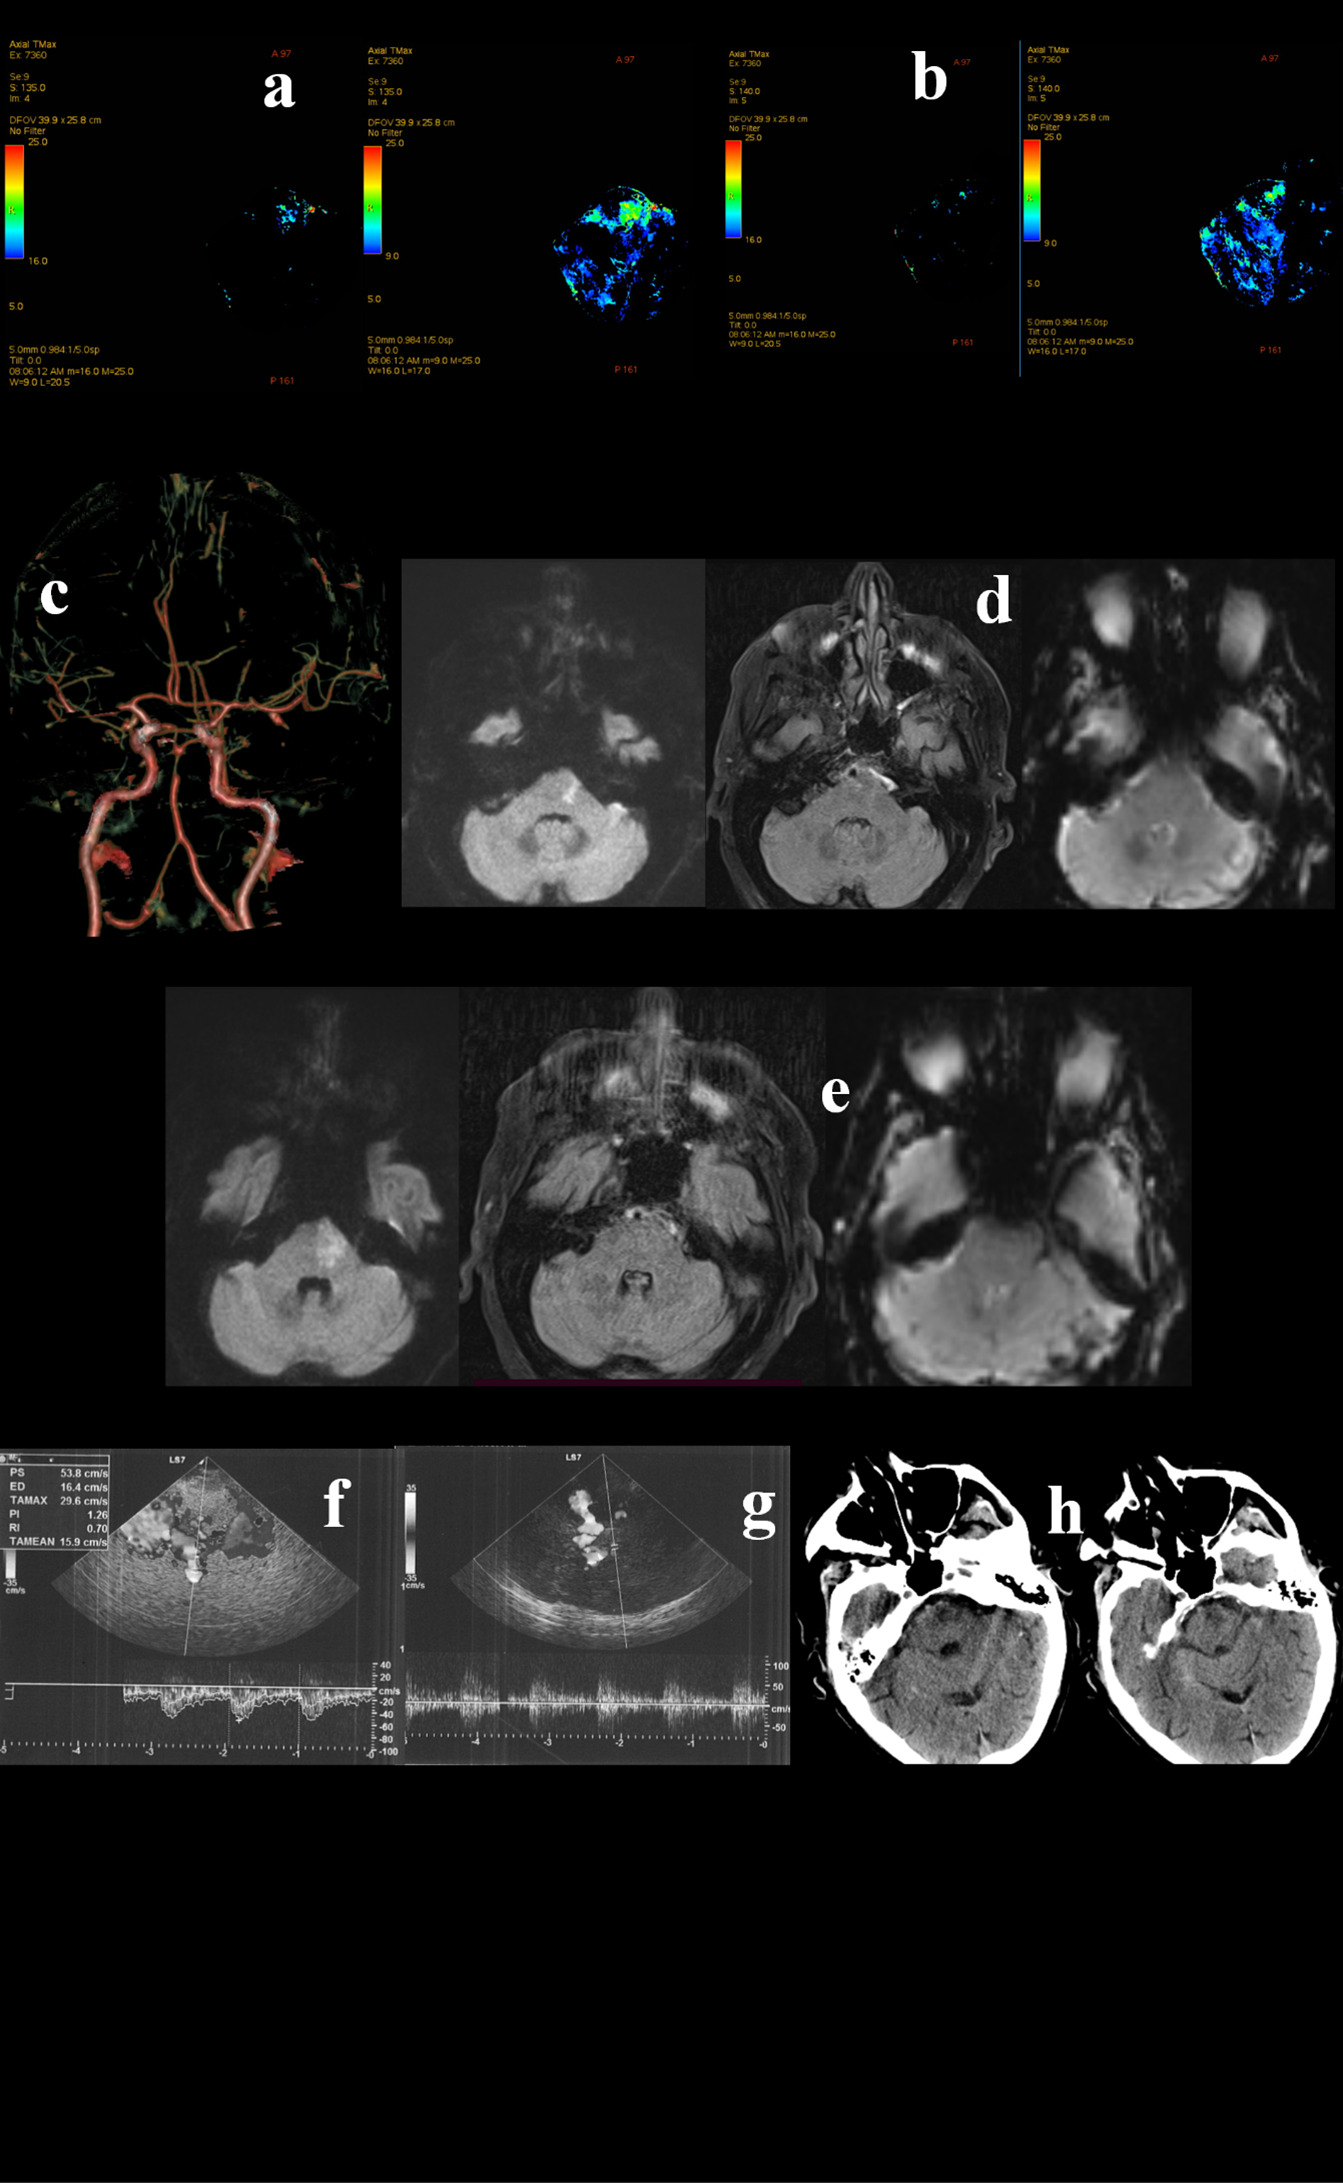

Figure 3. A 79-year-old Caucasian man awoke with right deviation of the head and right hemiparesis. His last known normal was 10 p.m. the previous night. His past medical history revealed arterial hypertension, diabetes mellitus, and dislypidemia. The patient was presented to the emergency department at 09:00 a.m. The neurological examination showed coniugate left gaze palsy, dysarthria, and right hemiparesis, with a fluctuating course. Urgent Head CT did not show acute lesions and the CT perfusion documented an area of ischemic core in the left pons (a) and penumbra in pons, medulla and bilateral superior cerebellar hemispheres (a,b). CTA documented distal basilar artery stenosis. The patient underwent urgent MRI which confirmed a right paramedian pontine DWI hyperintensity, in the context of which a moderate hyperintensity on FLAIR sequences was observed (c,d). Although basilar artery was associated with brainstem hypoperfusion, the FLAIR-positive lesion determined a significant risk for hemorrhagic transformation in case of revascularization. Hence, TCCS was performed and did not reveal hemodynamic demodulation in the proximal tract (f) and in the top (g) of basilar artery. Thus, DSA and PTAS were avoided. Dual antiplatet therapy was administered. In the following days the patient showed a gradual progressive improvement, with the evidence on a small lesion on control head CT (h).